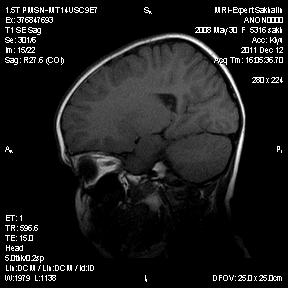

Девочка 3 года.В анамнезе -родовая травма-внутрижелудочковые кровоизлияния 1-2 ст.Задержка психического развития.Со слов мамы, "бывают истерики, хватается ручками за голову, особенно затылочную часть".Как интерпретировать изменения в желудочках, в задних рогах?Ликворную кисту ЗЧЯ отметила.

Киста не совсем киста, но нижняя ретроцеребеллярная цистерна незначительно расширена- я указала.

А вот гипоинтенсивное по Т2 в заднем роге левого бокового желудочка?В других последовательностях нет.

справа киста сосудистого сплетния -она же ксанутрогранулема,пртекаетбессимптомно.в эру доКТ и МРТ диагнстировались только на аутопсии,влевомсплетении -фокус пониженного МРС -возможно обезыствление или гемосидерин  ( ведь было кровоизлияние?)

Спасибо, Ирина!Было кровоизлияние, причем с обеих сторон.